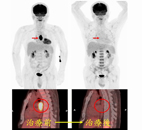

使用去氧葡萄糖全身正子掃描在診斷及治療癌症上的幫助(相關圖片)此男性病人在發現食道癌後接受了去氧葡萄糖正子斷層掃描以作為分期及治療前評估。治療前的正子斷層掃描發現食道有ㄧ段明顯葡萄糖代謝升高的腫瘤病灶。經過醫師給予合併化療與放射治療之後,可以看見原本呈高葡萄糖代謝性食道腫瘤幾乎完全消失,正子檢查結果明顯反應治療成效PET/CT正子掃描的安全性